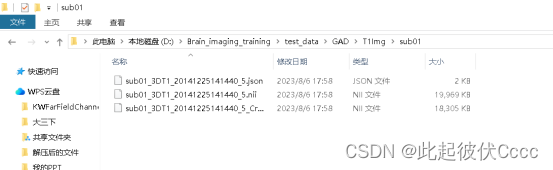

(1) 将工作路径切换至图像数据存在的地方,并在该路径下按如下图格式创建文件夹,其中T1Img文件夹中存放未经过格式转换的被试.dcm文件。

每个subxx文件存放被试的.dcm图像文件:

在与T1Raw相同文件夹的T1Img文件中生成了图像格式转换后的.nii文件,如下图所示:

其中sub01_3DT1_20141225141440_5_Crop_1.nii文件便是我们后期需要处理的.nii文件,用mricron软件查看图像如下图所示: